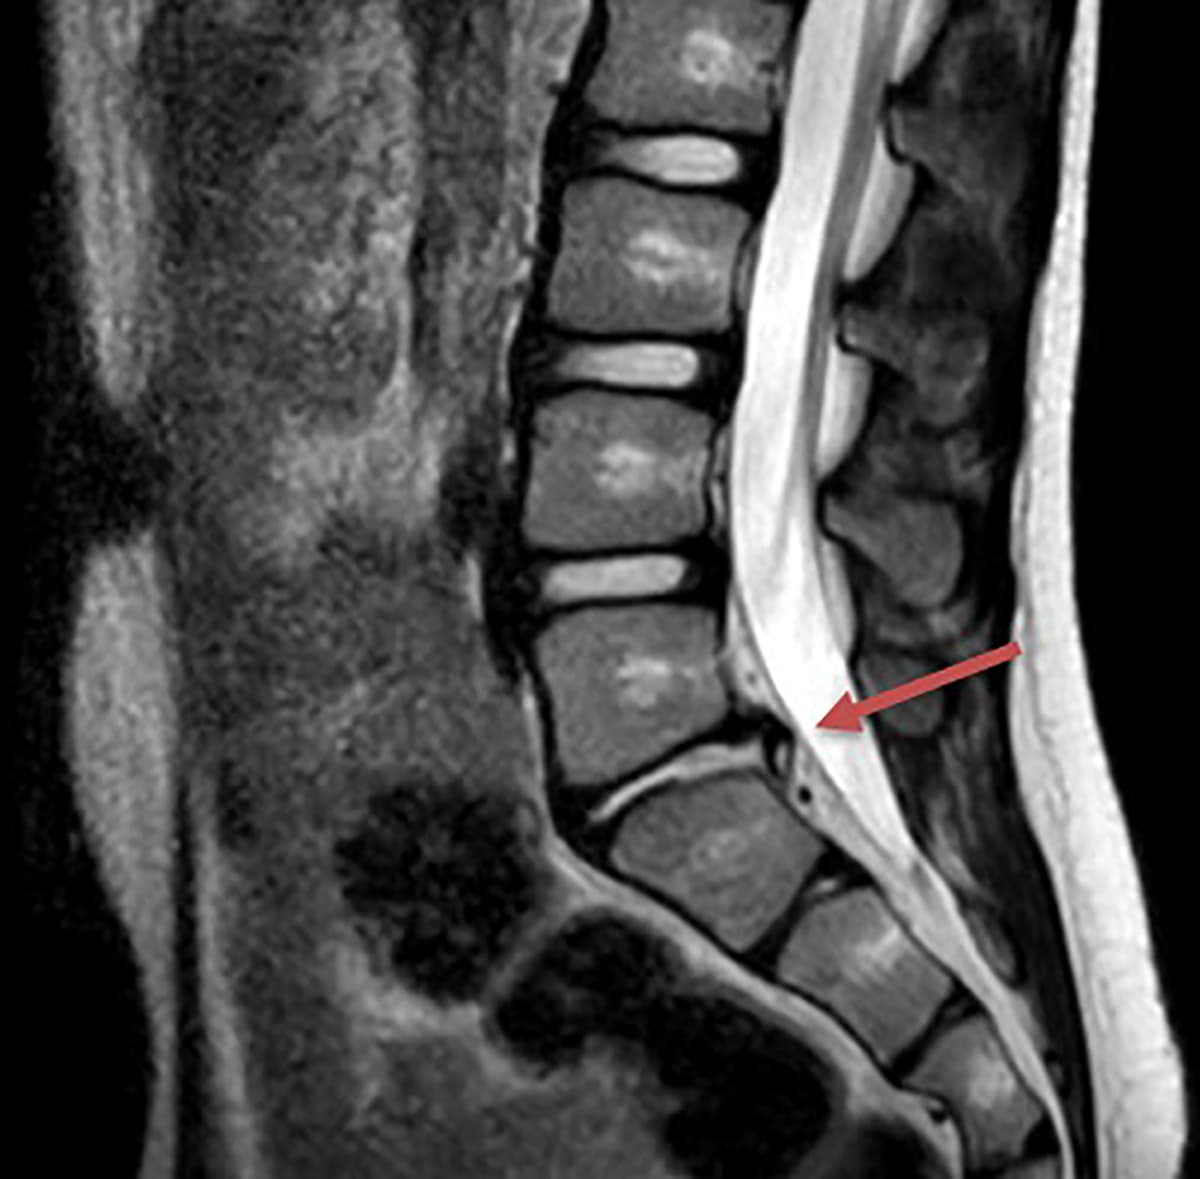

På mistanke om osteomyelitis blev der taget blodprøver og lavet MR-skanning af columna lumbalis. Skanningen viste diskusprolaps mellem L5 og S1. Efter konservativ behandling med træningsforløb var drengen ved den opfølgende tremånederskontrol smertefri, og der blev ikke foretaget flere kontroller i børneafdelingen.